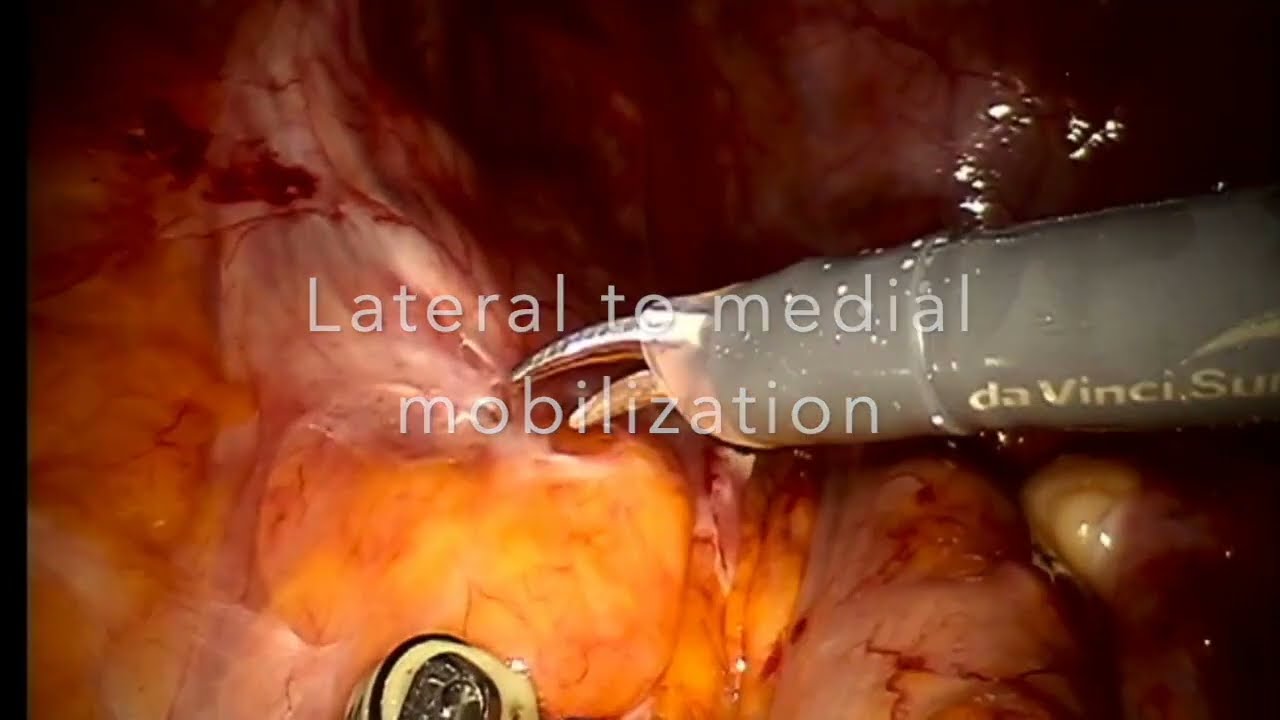

#187 Robotic Assisted Enbloc Dual Kidney Transplant Dr. Sreeharsha Harinatha

KS Awards, Robotics, Surgeon ';